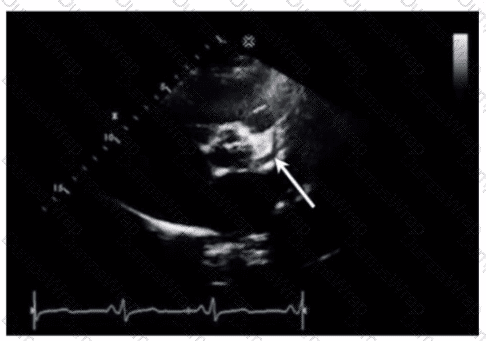

Which anatomic structure is represented by the arrow on this image?

DExplanation:

The echocardiographic image is a four-chamber view focusing on the mitral valve apparatus. The arrow points to the anterior leaflet of the mitral valve, which is typically more prominent, triangular in shape, and located adjacent to the aortic valve in the left ventricular outflow tract region.

The posterior leaflet of the mitral valve is generally smaller, has multiple scallops, and is located posteriorly relative to the anterior leaflet. The septal leaflet is part of the tricuspid valve on the right side of the heart. The "left leaflet" is a non-specific term and not an anatomical descriptor.

This differentiation between anterior and posterior leaflets is important for understanding mitral valve pathology and for interventions such as mitral valve repair. These features are clearly explained in echocardiography texts and ASE valve imaging guidelines【12:ASE Valve Imaging Guidelines†p.180-185】【16:Textbook of Clinical Echocardiography, 6e†p.200-205】.